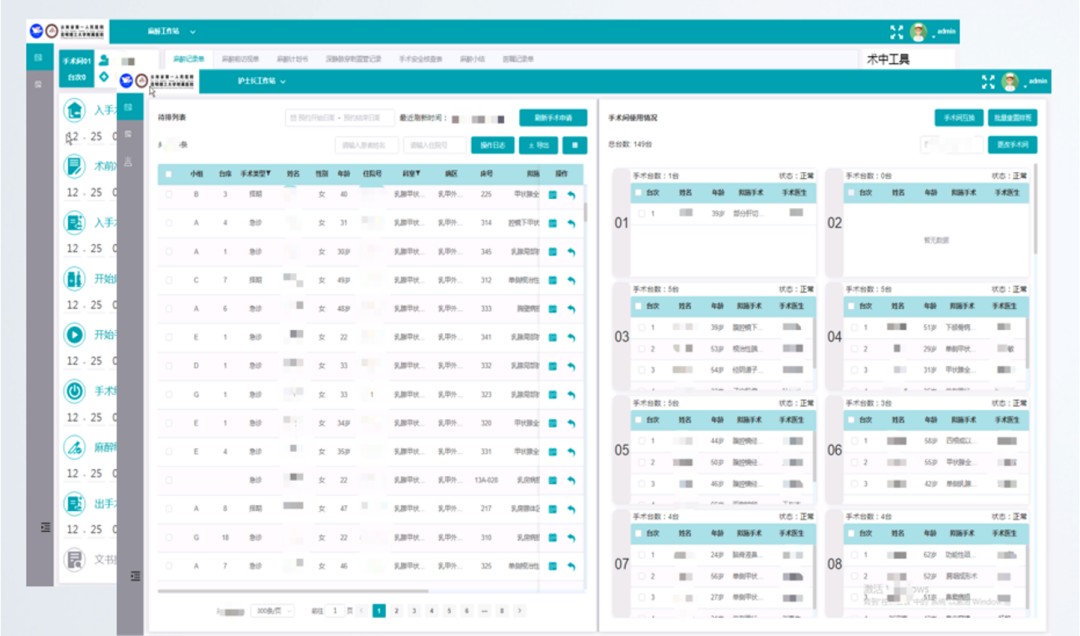

麻醉手术风险预测联合解决方案实现对手术麻醉全过程的闭环管理。该方案减轻了麻醉医生工作压力,协助麻醉医生完成术前评估和术后随访工作,制定更加科学的麻醉方案。同时该方案实现手术申请、手术麻醉安排、术中物资清点等业务的计算机管理,将工作人员从繁重的手工记录、统计中解脱出来。

另外该方案提供规培学员、研究生和进修医生入科前培训、入科考试、出科考试、自动统计工作量等的管理能力。方案支持针对多个患者进行同数据的多维度对比,生成各种单据、报表,极大方便了科室管理。该系统病人手术麻醉发生的费用信息可直接通过麻醉记录单产生相关费用,避免漏费和欠费的发生,方便医院进行成本核算。

(手术麻醉临床信息管理系统)